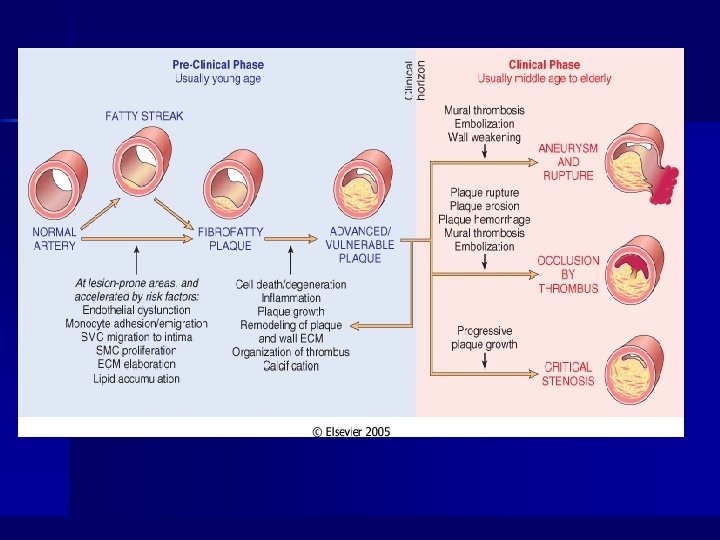

Atherosclerosis n n Arteries with a diameter above 1 mm Potentiated and caused by the risk factors Main cause of ischemic stroke Is thought to start around the age of 40

General Comments n Arteriosclerosis – Thickening and loss of elasticity of arterial walls – Hardening of the arteries – Greatest morbidity and mortality of all human diseases n Two major processes in plaque formation: – Intimal thickening – Lipid accumulation

Summary of Atherosclerotic Process n n n n n Multifactorial process (risk factors) Initiated by endothelial dysfunction Up regulation of endothelial and leukocyte adhesion molecules Macrophage diapedesis LDL transcytosis LDL oxidation Foam cells Recruitment and proliferation of smooth muscle cells (synthesis of connective tissue proteins) Formation and organization of arterial thrombi

Fibrous Plaques Complicated Lesions

Complicated Lesions